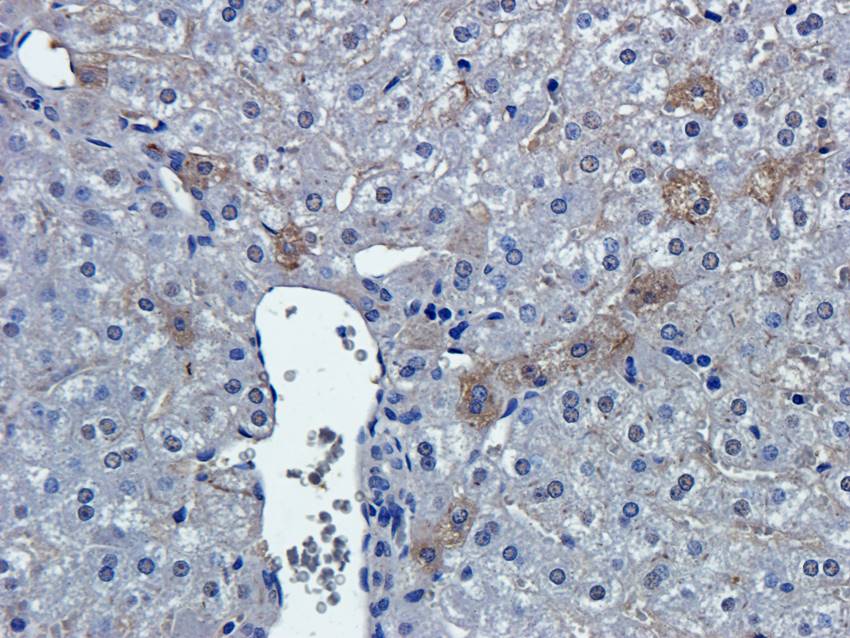

10 μg, 100 μg - Cubilin antibody [orb4997]Featured

ICC, IF, IHC-P, WB

Human, Mouse, Porcine, Rat

Rabbit

Polyclonal

Unconjugated